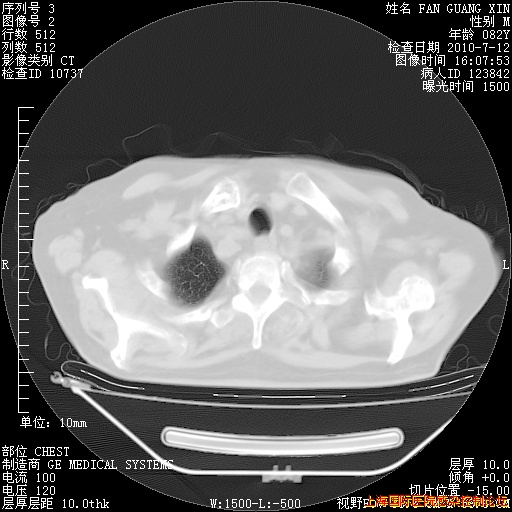

补发6月12日肺部CT肺窗

回复

6月12日肺窗